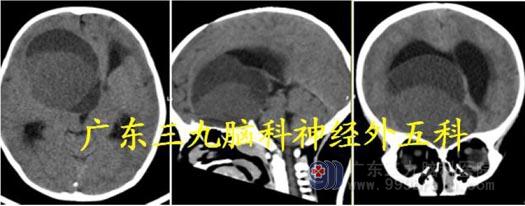

头颅MR:胼胝体压部及左侧枕顶叶示一团片状占位性病变,增强后病变呈明显较均匀

强化,范围约为6.4cm×4.5cm×3.6cm,周围示片状长T1 长T2 水肿信号影。胼胝体压

部及左侧枕顶叶、左侧颞叶、双侧额叶多发占位性病变,考虑肿瘤性病变,淋巴瘤可能。

头颅CT:胼胝体压部及左侧颞枕顶叶占位性病变呈偏等密度为主。